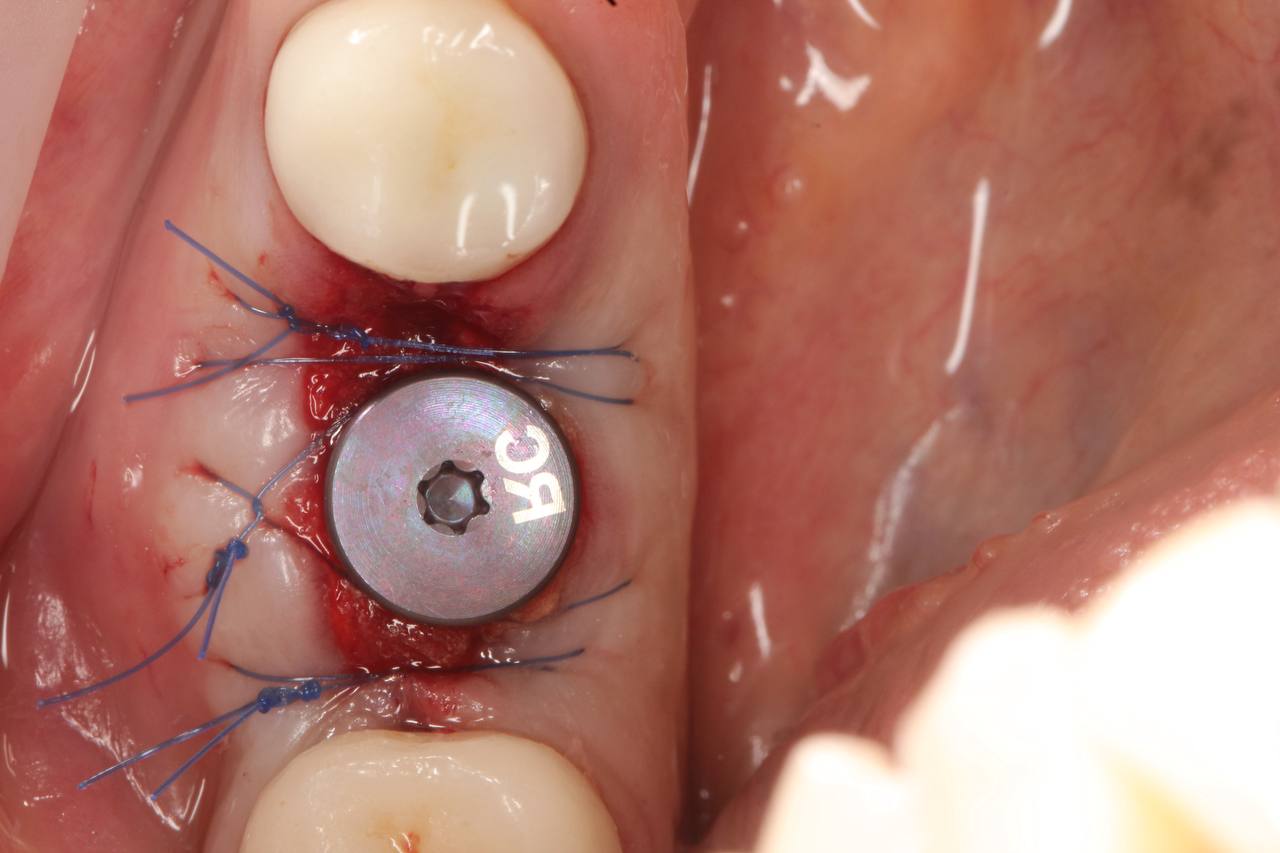

• Установка имплантата

• Изготовление индивидуального формирователя десны, сохраняющего объем и контур тканей